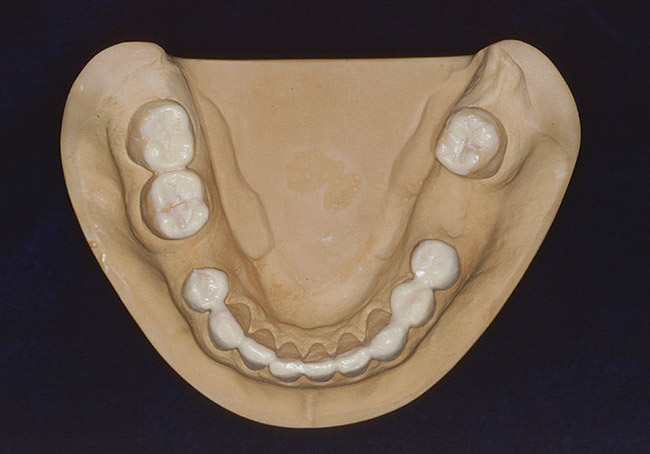

Figure 4. Occlusal contacts occur generally on the posterior teeth, most often on the first molars, followed by the second molars and premolars.

Figure 4